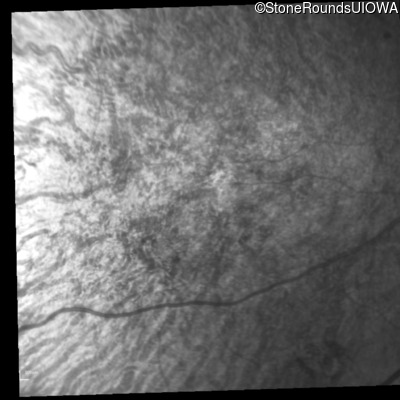

Infrared Fundus Photograph - Right - 10/200

Exemplar